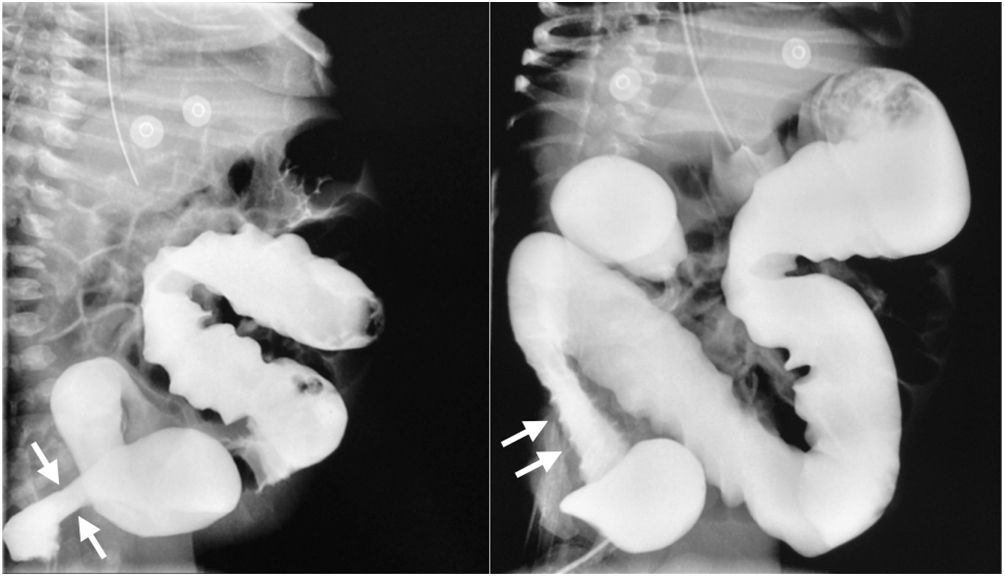

A plain abdominal x-ray was ordered, revealing important intestinal segment dilation (Fig. 1A). An orogastric tube was placed, with abundant output of bile, and a transrectal tube improved the abdominal distension (Fig. 1B). The infant had clinical signs of low cardiac output that responded to dobutamine infusion and presented with oliguria and elevated serum creatinine and blood urea nitrogen. Thyroid panel results were TSH 404 mIU/mL, total T4 0.420ng/dl, T4 0.058ng/dl, total T3 0.195ng/dl, T3 0.321pg/mL, for which treatment with levothyroxine was indicated. Feeding was started with extensively hydrolyzed formula in continuous infusion one week after her admission. Given the clinical presentation consistent with Hirschsprung’s disease, a contrast-enhanced barium enema was ordered that revealed an apparent transition zone in the rectosigmoid colon (Fig. 2), and so rectal irrigations were started. A rectal biopsy was taken, and high-resolution anorectal manometry was performed, documenting the rectoanal inhibitory reflex. Pericardial effusion, anemia, elevated direct bilirubin, and elevated transaminases were detected in the complementary evaluations.

The coexistence of hypothyroidism and Hirschsprung’s disease has been reported. Given that the thyroid hormones are essential for histogenesis, cell migration, and the cytoarchitecture of the central nervous system, the lack of those hormones has been suggested to favor the development of Hirschsprung’s disease, due to effects on gene expressions, ligands, receptors, apoptotic factors, or extracellular matrix proteins that affect cell migration or differentiation5. Thus, we had to rule out Hirschsprung’s disease in our patient, which we did, through rectal biopsy and anorectal manometry.